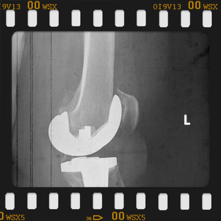

Eklem yüzeyleri özel kılavuzlar yardımı ile temizlendikten sonra metal protez eklem yüzeylerine bir kemik çimentosu ile adapte diyoruz. Bu iki metal yüzeyin sürtünmesini azaltmak için polietilenden yapılmış özel bir plastik tabakayı sisteme dahil ediyoruz.

Büyütmek için üzerine tıklayınız.